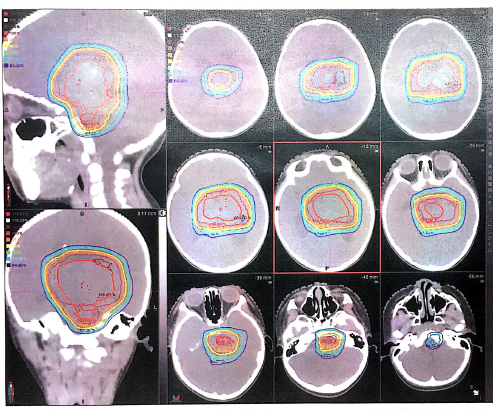

2021年1月25日至3月10日:对该患儿进行了50.40GyE,28次的质子放疗。

图4

图5

质子放疗剂量分布图

图6

图7